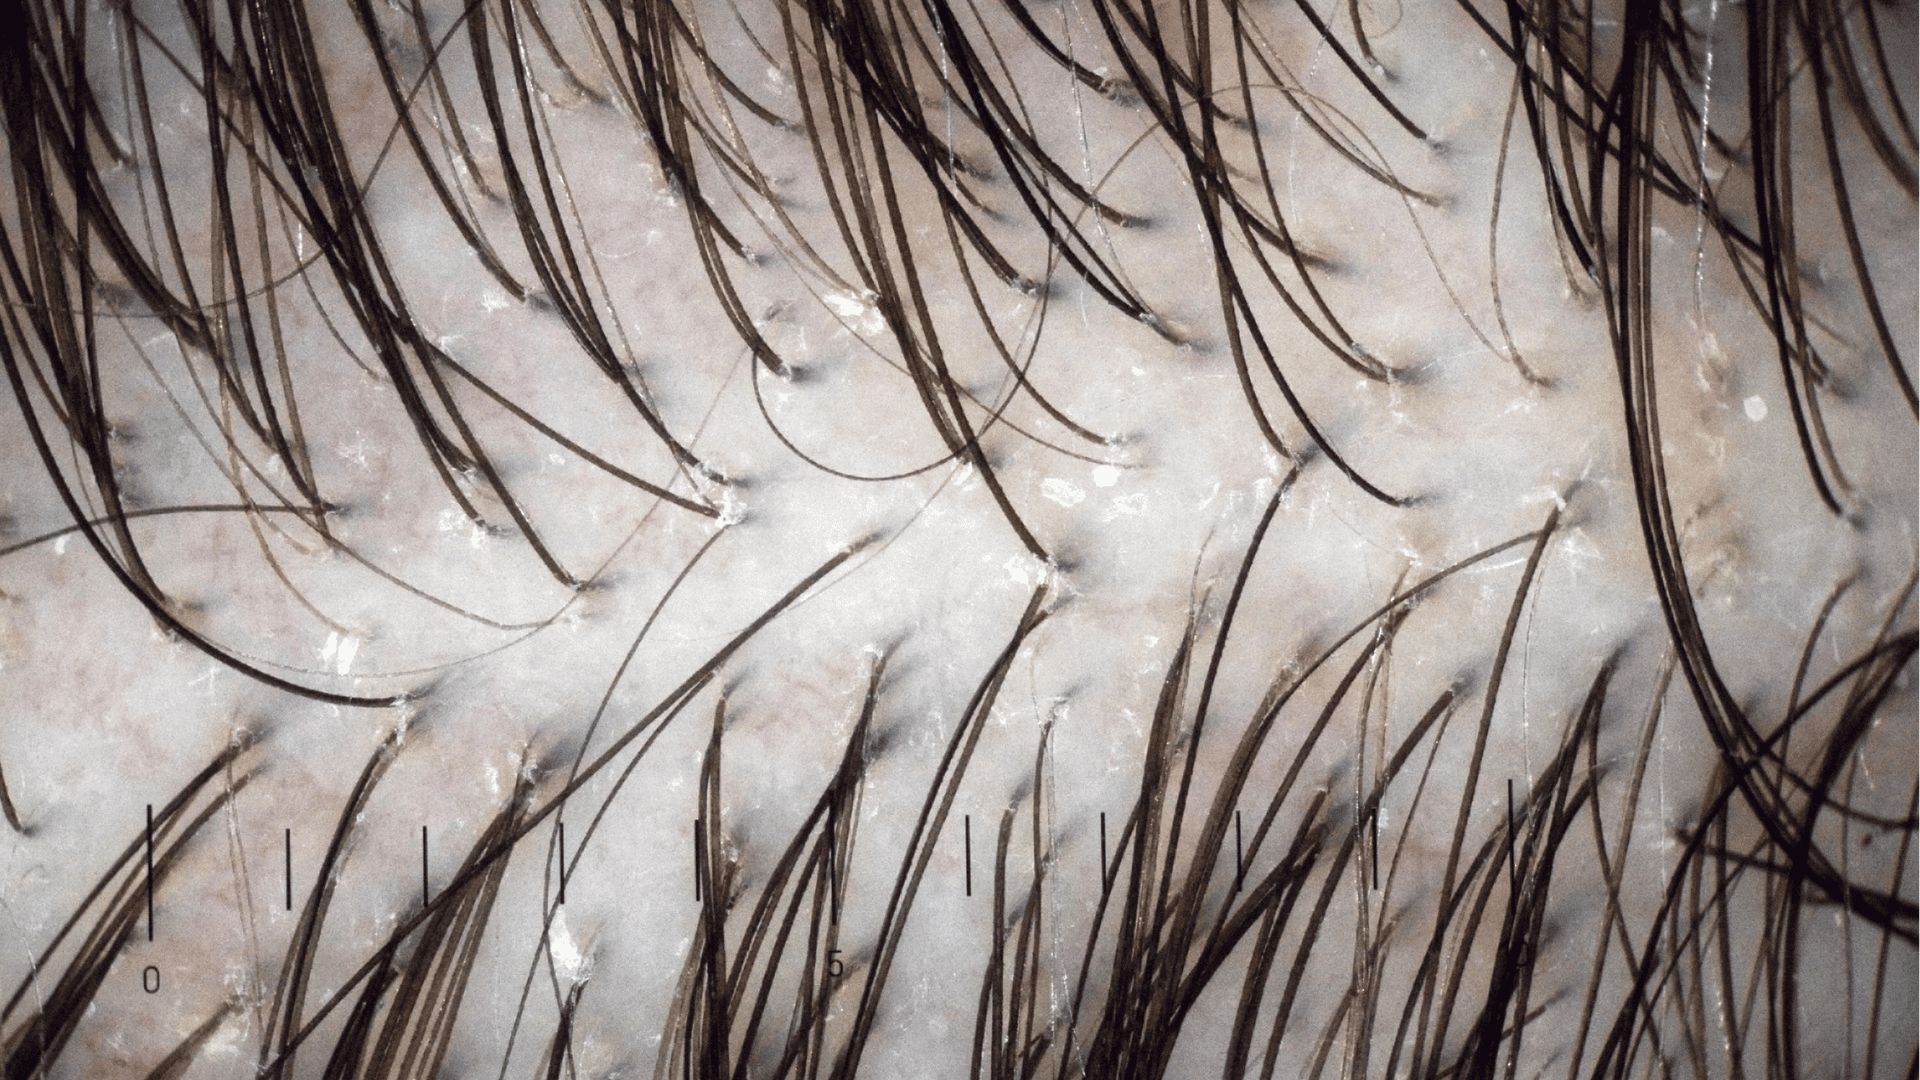

zbliżenie na skórę głowy z pokazaniem mieszków włosowych

Trichoskopia wykonywana jest za pomocą ręcznego dermatoskopu (specjalistycznej "lupy" dermatologicznej) i stanowi podstawowe badanie stanu zdrowia i jakości skóry głowy, mieszków włosowych oraz włosów.

Wideotrichoskopia to rozwiązanie cyfrowe, które wykonywane jest za pomocą cyfrowej kamery podłączonej do komputera. Pozwala dermatologowi-trychologowi nie tylko obejrzeć skórę głowy w znacznym powiększeniu, ale także zapisać zdjęcia z badania, dzięki czemu w przyszłości, porównując zdjęcia, będzie można łatwo zweryfikować efektywność stosowanej terapii.

Trichoskopia to medyczne badanie wykonywane najczęściej przy użyciu dermatoskopu (specjalistycznej lupy dermatologicznej), który pozwala dokładnie ocenić strukturę włosa i stan skóry głowy.

Wideotrichoskopia to w uproszczeniu rozszerzenie tej metody z wykorzystaniem wideodermatoskopu (kamery podłączonej do komputera), pozwalającego nie tylko na znaczne przybliżenie obrazu i dokładną analizę skóry głowy, mieszków włosowych oraz włosów, ale także dającego możliwość zapisania zdjęć z badania w celu porównania ich w przyszłości z wynikami badań kontrolnych (np. w celu zweryfikowania skuteczności terapii).